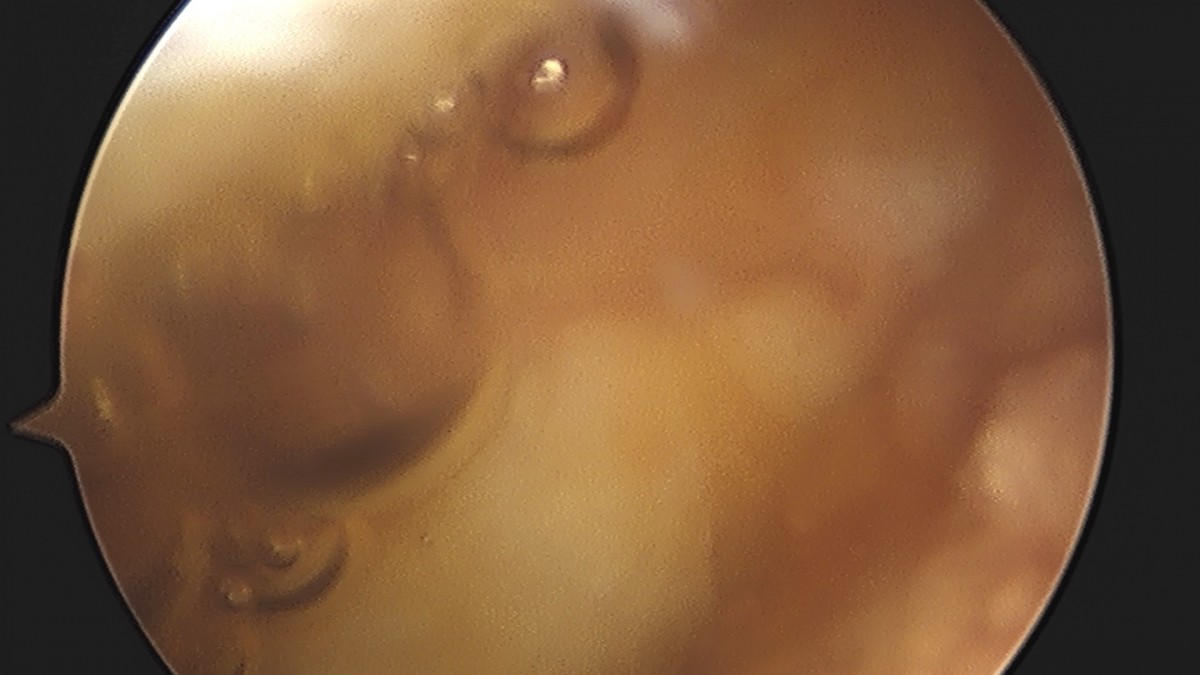

이재상원장님 무릎 반월상 연골판 절제술 박상O 환자

dae765e4d9ac96aee867c9d6292d8784_1758006442_9544.jpg